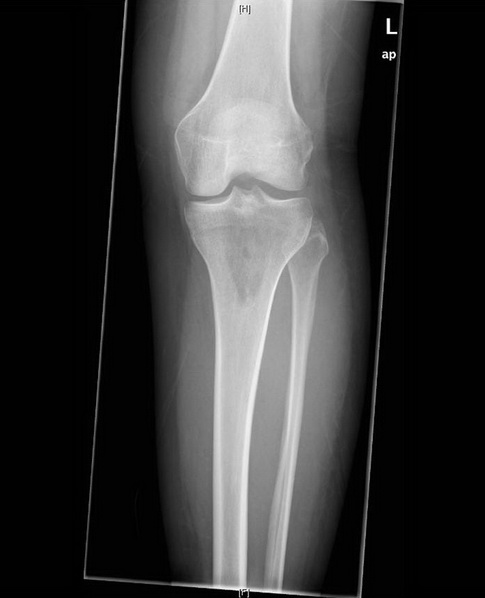

Röntgen in zwei Ebenen

Beachte die Aufhellung in der proximalen Tibia

Postoperative Röntgenkontrolle: Im Vergleich zu den Voraufnahmen zeigt sich, dass das bioptisch nachgewiesene Chondrosarkom im Bereich der proximalen Tibia dorsalseitig vollständig resiziert werden konnte. Kein Hinweis auf Fissuren oder Frakturen.